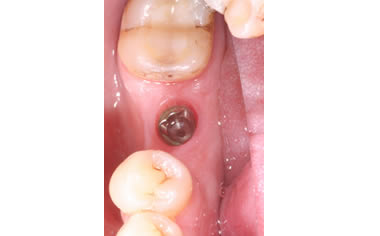

More back teeth replaced by dental implants

Case Five (4 images)